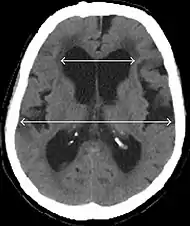

- Imaging from magnetic resonance imaging (MRI) or computed tomography (CT) is needed to demonstrate enlarged ventricles and no macroscopic obstruction to cerebrospinal fluid flow. Imaging should show an enlargement to at least one of the temporal horns of lateral ventricles, and impingement against the falx cerebri resulting in a callosal angle ≤ 90° on the coronal view, showing evidence of altered brain water content, or normal active flow (which is referred to as "flow void") at the cerebral aqueduct and fourth ventricle.

MRI scans are preferred. The distinction between normal and enlarged ventricular size by cerebral atrophy is difficult to ascertain. Up to 80% of cases are unrecognized and untreated due to difficulty of diagnosis.[7] Imaging should also reveal the absence of any cerebral mass lesions or any signs of obstructions. Although all patients with NPH have enlarged ventricles, not all elderly patients with enlarged ventricles have primary NPH. Cerebral atrophy can cause enlarged ventricles, as well, and is referred to as hydrocephalus ex vacuo.